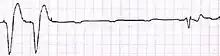

Setup for doing an ECG off the device Example of ECG off the device a) free floating in the RV b) in contact with the RV wall

Example of ECG off the device a) free floating in the RV b) in contact with the RV wall It is possible to place the lead in the coronary sinus, normal (left) dilated (right). Such placement is okay.